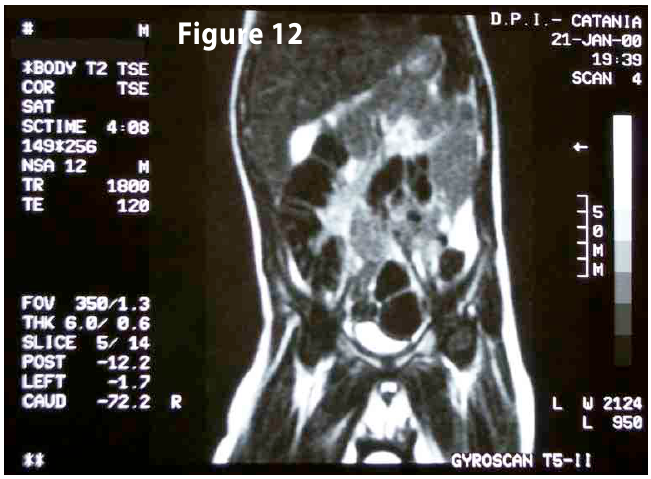

Complete objective response of neuroblastoma to biological treatment.

Figure12